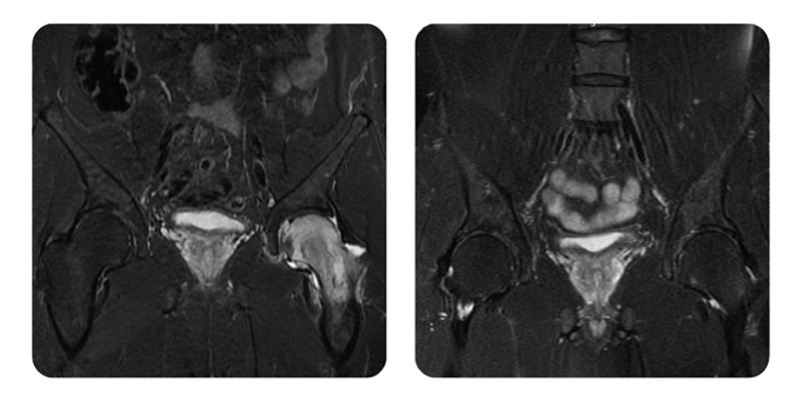

Prima

Dopo

G.A., 44 anni - Necrosi della testa del femore sinistro, stadio 1/2

Diagnosi: Necrosi della testa femorale sinistra, stadio I/II.

Rezultat: Guarigione completa.

Il paziente ha riferito una riduzione significativa del dolore già dalle prime sedute, seguita da miglioramento della mobilità. La guarigione completa è stata confermata all'esame RMN.